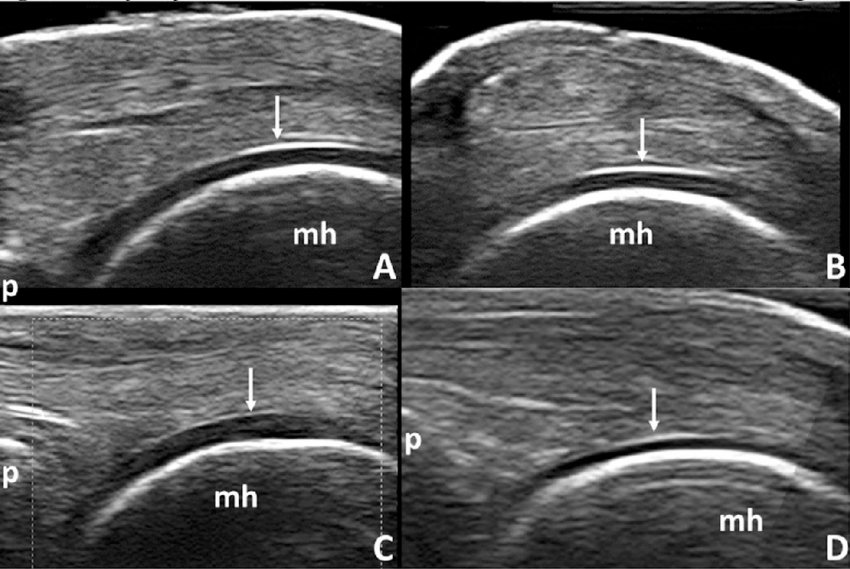

ultrasound: articular cartilage

Anechoic (black) layer overlying the periosteum